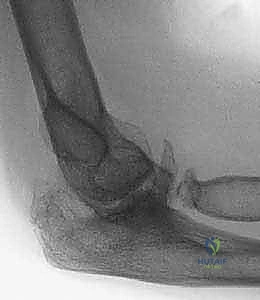

4. التكلس العظمي المغاير (Heterotopic Ossification - HO)

هي حالة طبية غريبة ومعقدة حيث ينمو عظم جديد في الأنسجة الرخوة (مثل العضلات، الأربطة، أو الكبسولة) خارج الهيكل العظمي الطبيعي، وذلك كاستجابة غير طبيعية للجسم بعد التعرض لصدمة قوية، حروق، أو إصابات في الدماغ والحبل الشوكي.

* النتيجة: يؤدي هذا العظم النامي إلى تيبس الكوع بالكامل (Ankylosis)، حيث يصبح المفصل بمثابة كتلة عظمية واحدة صلبة لا تتحرك إطلاقاً.

| الأشعة السينية العادية (X-Rays) | تقييم الهيكل العظمي الأساسي، الكشف عن الكسور القديمة، المسامير والشرائح السابقة، ومدى تآكل المفصل. | كخطوة أولى وأساسية في جميع الحالات. وتؤخذ من زوايا متعددة. |

| الأشعة المقطعية (CT Scan) مع بناء ثلاثي الأبعاد 3D | توفير تفاصيل دقيقة للغاية عن شكل العظام، التكلسات المغايرة، التئام الكسور، وتخطيط حجم ونوع المفصل الصناعي أو الشرائح المطلوبة. | ضروري جداً قبل التخطيط لجراحات التبديل الكلي للكوع أو إزالة التكلسات العظمية الضخمة. |